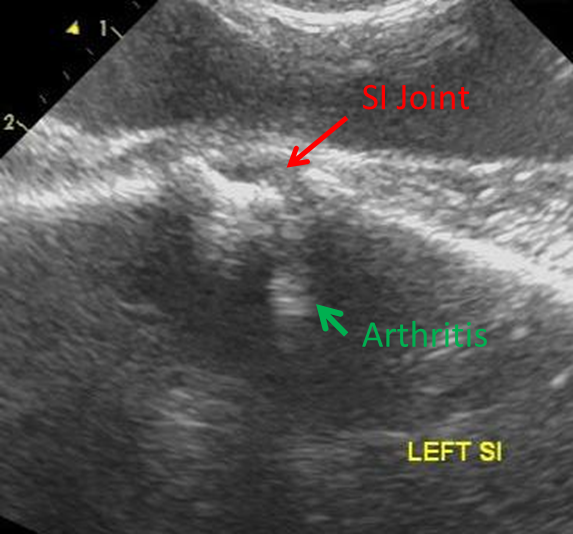

From mskultrasound.net

From michaelporterdvm.blogspot.com